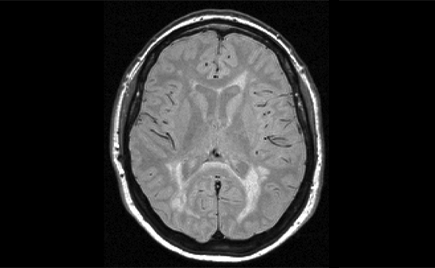

The Role of Imaging in the Diagnosis and Treatment of Multiple Sclerosis

During this hour-long webinar sponsored by Cortechs.ai, an expert panel of neuroradiologists will review the use of automated volumetric post-processing for the diagnosis and longitudinal assessment of multiple sclerosis and will address potential correlations between white and gray matter lesion counts and volumes, lesion burden and brain structure volumes.